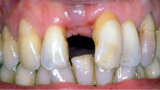

Triumfy a tragédie v implantologii